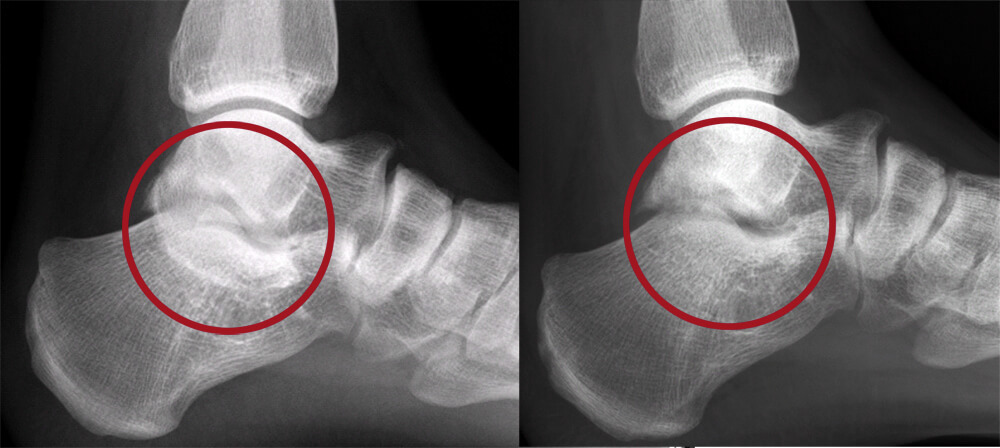

Bij deze patiënt is de vergroeiing tussen het sprongbeen en het hielbeen operatief verwijderd.